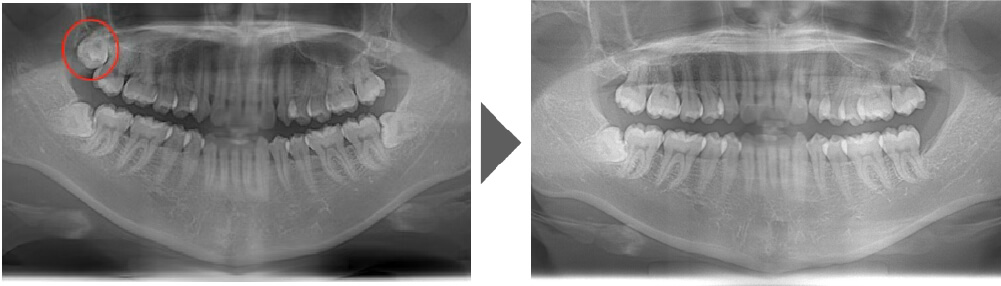

抜歯症例①

ご覧いただいた通り、歯根の先が隣の歯と比べても湾曲しています。 通常よりも抜歯の難易度が上がる症例です。

【抜歯所要予約時間】

15分

(麻酔の時間があるので処置自体はもっと短いです)